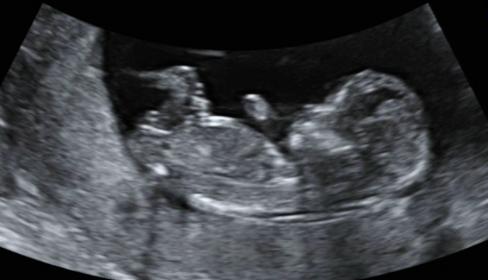

Here are some photos from my 12w ultrasound...I have a son and am hoping for a girl. Opinions, pretty please? I am dying to know!

Attachment 16293

Looks girly! :)

I guess boy due to the blob on top. Sorry that isn't what you are hoping to hear!!

I think maybe girl.....

Girl! What did the dr say?

I am going with boy.

I'm thinking boy too, hope I'm wrong tho and you get your girl

I am leaning girl.

I don't really know how to read these things but just looking at yours if I had to guess i'd say girl.

my guess is girl!

Thanks everyone, 6 girl and 3 boy guesses...it will be interesting to see what it is. I'll update you when I know (end of February) :)

UPDATE: we found out today that we are having a girl!!!! Thanks for all your predictions, very excited!